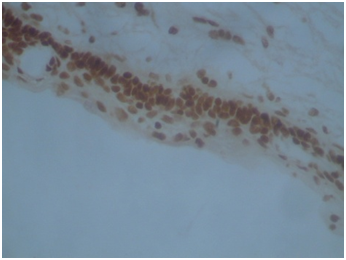

HMW cytokeratin was positive in all 22cases in all squamous parts (Figure 4). Cytokeratin 19 was positive in PBC and SR but negative in SMS and WK parts (Figure 5). Cytokeratin 20 was negative in all squamous parts. LMW cytokeratin: was positive in the PBCs and SMS but reduced in SR and negative in WK in 17/22cases (Figure 6). Cytokeratin 7 was positive in the SR but not in the PBC, SMS or WK in 19/22cases (Figure 7). Cytokeraitn 5/6 was positive in all three layers SMS, SR and PBC but negative in wet keratin in 22/22 cases (Figure 8).EMA was positive in SR and WK, but negative in PBC and SMS in 17/22cases (Figure 9).p63 was positive in PBC and SR cells, but negative in WK and SMS in 16/22cases (Figure 10).p16 was positive in PBC and SR in 15/22cases (Figure 11).Twelve cases show positive p53 immunostainings with range 2%-50% of the cells (Figure 12). Ki67 showed more than 10% positivity in 13cases (Figure 13) and low positivity or negative in 12cases. B-catenin was positive in PBC in 11cases in cytoplasmic and nuclear pattern and was positive in 11cases in cytoplasmic pattern only.

Figure 5 Cytokeratin 19 was positive in PBC & SR but negative in SMS & WK part.